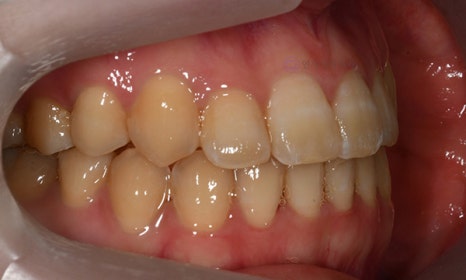

다음 케이스 역시 위 아래 중심선의 차이가 있어서 비대칭이 있어 보이는 케이스입니다. 중심선의 차이 뿐 아니라 앞니 및 어금니 부위에 거꾸로 물리는 반대교합이 관찰되고 있었습니다(원래는 위 치아가 아래 치아를 덮는 것이 정상적인 교합이나, 반대교합이란 위 치아가 아래 치아보다 더 안쪽으로 들어가서 물리는 교합을 말합니다).

2020.2

얼굴의 중심선과 위 치아의 중심선은 일치하여, 오른쪽 아래 작은 어금니를 발치하여 그 공간으로 아래 치열을 이동시켜줌으로써 중심선 및 교합을 개선하였습니다.